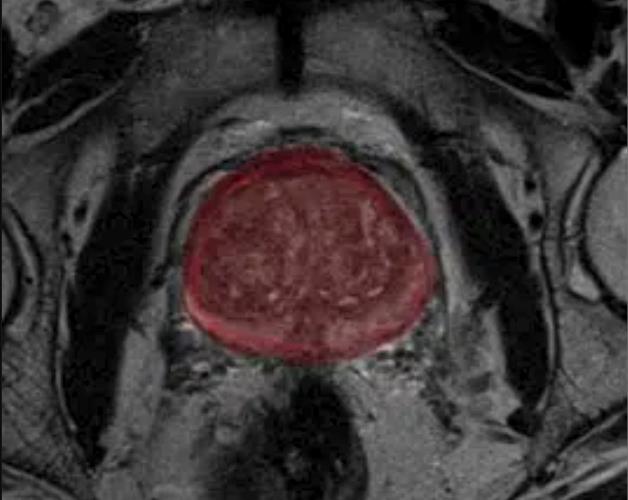

Despite increased use of preoperative magnetic resonance imaging (MRI) in recent years for patients undergoing surgery for prostate cancer, a study found that over 70 percent of a large Medicare population with prostate cancer did not have a preoperative MRI scan as of 2015.

In addition to segmentation of the prostate, the artificial intelligence (AI)-enabled advance reportedly facilitates PI-RADS scoring by assessing the size and intensity of possible lesions.